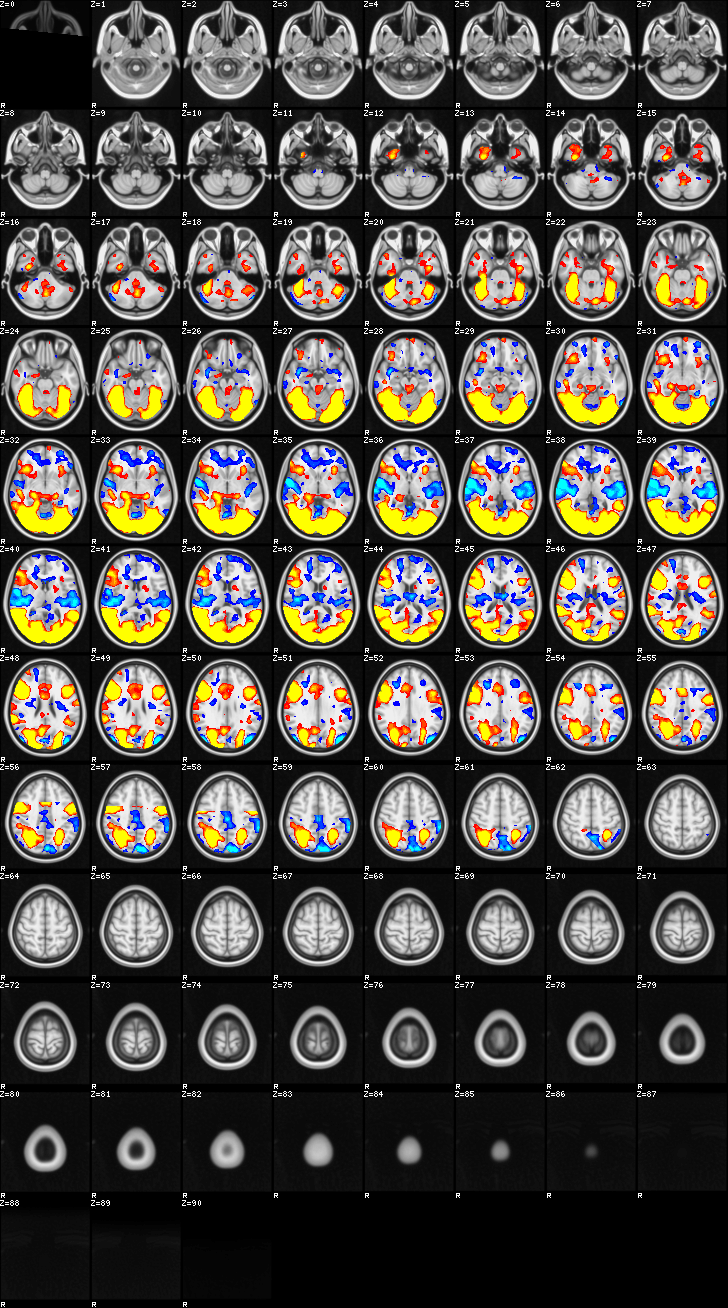

Fixed Effect¶

ATM it is 8 subjects, 8 mm FWHM spatial smoothing, preliminary results only

Images thresholded abs value > 2.3 and colormap goes from 2.3 to 5 (red->yellow) or -2.3 to -5 (blue->lightblue)

03-self¶